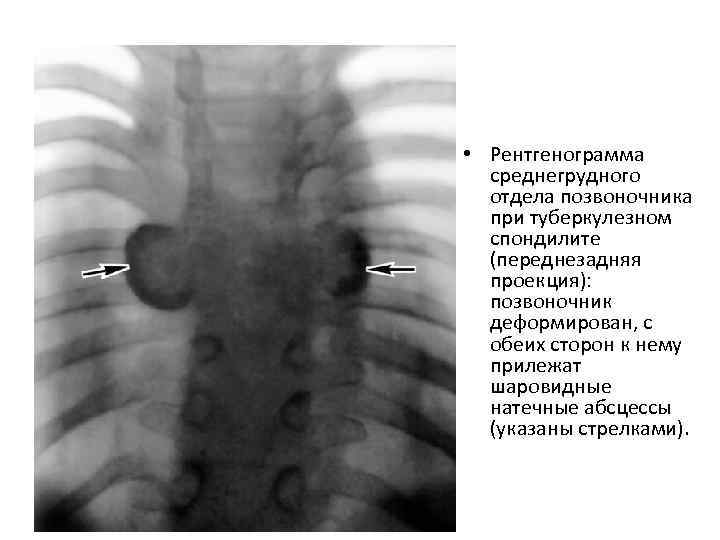

• Рентгенограмма среднегрудного отдела позвоночника при туберкулезном спондилите (переднезадняя проекция): позвоночник деформирован, с обеих сторон к нему прилежат шаровидные натечные абсцессы (указаны стрелками).

• Рентгенограмма среднегрудного отдела позвоночника при туберкулезном спондилите (переднезадняя проекция): позвоночник деформирован, с обеих сторон к нему прилежат шаровидные натечные абсцессы (указаны стрелками).

Спондилолитическая фаза • Спондилолитическая фаза (разрушение тела позвонка и переход процесса на межпозвонковые диски и окружающие мягкие ткани). • Кроме общих симптомов характеризуется появлением болей при наклоне туловища и ограничение движений из-за болей в позвоночнике. • При осмотре определяется искривление линии позвоночного столба, выступание остистого отростка, горб. • Для этой фазы характерен также "симптом вожжей" - напряжение мышц спины в виде тяжей, идущих от углов лопаток к поражённому позвонку. При надавливании на остистый отросток разрушенного позвонка пациент ощущает боль. • На спондилолитическом этапе туберкулёза позвоночника появляются натёчные абсцессы и свищи. Смещение тел позвонков может привести к сдавлению спинного мозга и развитию параличей конечностей, нарушениям функций тазовых органов. • На рентгенограмме определяется деструкция тел позвонков - признак патологического компрессионного перелома позвоночника, тени натёчных абсцессов.

Спондилолитическая фаза • Спондилолитическая фаза (разрушение тела позвонка и переход процесса на межпозвонковые диски и окружающие мягкие ткани). • Кроме общих симптомов характеризуется появлением болей при наклоне туловища и ограничение движений из-за болей в позвоночнике. • При осмотре определяется искривление линии позвоночного столба, выступание остистого отростка, горб. • Для этой фазы характерен также "симптом вожжей" - напряжение мышц спины в виде тяжей, идущих от углов лопаток к поражённому позвонку. При надавливании на остистый отросток разрушенного позвонка пациент ощущает боль. • На спондилолитическом этапе туберкулёза позвоночника появляются натёчные абсцессы и свищи. Смещение тел позвонков может привести к сдавлению спинного мозга и развитию параличей конечностей, нарушениям функций тазовых органов. • На рентгенограмме определяется деструкция тел позвонков - признак патологического компрессионного перелома позвоночника, тени натёчных абсцессов.